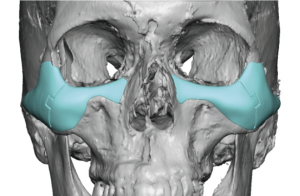

Eppley-Style Custom Implants for NOV

The core principle is not simply augmenting the infraorbital rim, but reconstructing the entire midface support platform in a continuous, anatomically blended way.

- Treat NOV as a global skeletal deficiency rather than a localized defect

- Create a smooth, continuous augmentation from:

- Medial infraorbital rim ? central rim ? lateral rim

- Extend inferiorly and laterally onto the cheek

- Avoid step-offs or isolated projection that appears unnatural

Implant Design Components (Single Integrated Piece)

Shape and Surface Characteristics

Contouring

- Fully customized based on CT anatomy

- Accounts for asymmetry, rim depth, and globe position

Feathered Edges

- Minimize palpability and visibility

- Especially important along inferior and lateral borders

Thickness Gradient

- Maximum thickness at the infraorbital–cheek junction

- Gradual tapering medially, laterally, and inferiorly

Severe NOV

- Full upper midface wraparound design

- Strong cheek augmentation

- Lateral arch extension

- Greater inferior maxillary expansion